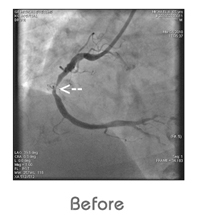

Coronary Angiogram

Angiogram is the gold standard for diagnosis of heart disease due to block. An easily detectable dye is injected into the artery through a catheter.